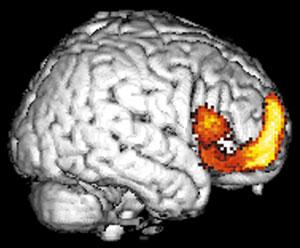

Именно наличие клиники во многом определяет возможности фундаментальных и прикладных исследований ИМЧ. Поэтому прежде всего несколько слов о ней. У нас прекрасные высококвалифицированные доктора и медсестры. Без этого нельзя: ведь мы на переднем крае, и нужна высочайшая квалификация, чтобы выполнять нерутинное, новое. У нас выполняются практически все стандартные манипуляции и наряду с ними и хирургическое лечение эпилепсии и паркинсонизма, проводятся психохирургические операции, в том числе и хирургическое лечение обусловленного героином обсессивно-компульсивного синдрома, знаменитая «пересадка мозга», точнее имплантация фетальной мозговой ткани, лечение магнитости-муляцией мозга, лечение афазии с помощью электростимуляции и многое другое. Накоплен десятилетний опыт клинических обследований с помощью позитронно-эмиссионной томографии. На рисунках приведена малая толика того, что может диагносцировать этот метод томографии. У нас лежат тяжелые больные, и мы стараемся помочь с помощью вышеперечисленных методов даже тогда, когда все остальные попытки были неудачны. Конечно, это удается не всегда. Но безграничных гарантий в лечении людей дать невозможно, а если кто-то дает их, это всегда вызывает очень серьезные сомнения.

Вообще, благодаря технике позитронно-эмиссионнной томографии (или сокращенно ПЭТ), стало возможно детальное изучение одновремено всех областей мозга, отвечающих за сложные “человеческие” функции мозга. Суть метода состоит в том, что малое количество изотопа вводят в вещество, участвующее в химических превращениях внутри клеток мозга, а затем наблюдают, как меняется распределение этого вещества в интересующей нас области мозга. Если к этой области усиливается приток глюкозы с радиоактивной меткой - значит, увеличился обмен веществ, что говорит об усиленной работе нервных клеток на этом участке мозга.

А теперь представьте, что человек выполняет какое-то сложное задание, требующее от него знания правил орфографии или логического мышления. При этом у него наиболее активно работают нервные клетки в области мозга, “ответственной” именно за эти навыки. Усиление работы нервных клеток можно зарегистрировать с помощью ПЭТ косвенно, по увеличению локального кровотока в активированной зоне. (Более ста лет назад было показано, что усиленная работа нервных клеток приводит к увеличению локального мозгового кровотока в этой области.)

Таким образом, удалось определить, какие области мозга “отвечают” за синтаксис, орфографию, смысл речи и за решение других задач. Мы предъявляем испытуемым различным образом организованные задания, при выполнении которых необходимо «задействовать» определенные свойства речи. Например, отдельные слова, предложения, связный текст. Сравнивая ПЭТ изображения, получаемые при этой деятельности, мы можем определить, где в мозге происходит обработка отдельного слова, где синтаксиса, а где смысла текста. Видны зоны, активирующиеся при предъявлении слов, неважно, надо ли было их читать или нет. Зоны, отвечающие за смысл текста, и другие. Интересно, и это будет рассмотрено ниже, что удалось обнаружить зоны, активирующиеся, чтобы «ничего не делать».

В исследованиях мозговых механизмов восприятия речи по результатам ПЭТ исследования с использованием локального кровотока обнаружено, что при чтении текста основные изменения происходят в области левой височной доли (38, 22, 43, 41, 42, 40 и 38 поля), 3, 4, 6, 44, 45, и 46 полей и справа в области 22, 41, 42, 38, 1, 3, и 6 полей. Сопоставление с данными других исследователей позволяет соотносить некоторые из этих результатов с процессами запоминания, чтения слов, понимания смысла. Появилась возможность выделить области, связанные с восприятием смысла и запоминанием текста, от областей, которые связаны с обработкой отдельных слов. Эти результаты коррелируют с полученными ранее с помощью анализа нейронной активности. Были также подтверждены результаты, полученные при исследовании нейронной активности, о вовлечении в обеспечение речи, наряду с классическими зонами, участков мозга, расположенных в других областях. При исследовании мозгового обеспечения речи картированы области коры мозга человека, участвующие в обеспечении различных стадий анализа орфографиче-ских и синтаксических характеристик. Показано, что медиальная экстрастриарная кора вовлечена в обработку орфографической струк-туры слов; значительная часть левой верхневисочной коры (зона Вернике) наиболее вероятно участвует в произвольном семантическом анализе, и менее вероятно - обработке синтаксической структуры; нижняя лобная кора левого полушария является звеном системы вербального семантического анализа, ее возможное участие в синтаксической обработке ограничено обработкой словоформ и функциональных слов, но не порядка их следования в предложении; в определение синтаксической структуры фразы на основе анализа порядка следования слов вовлечена передняя часть верхневисочной коры. На основе анализа мозгового кровотока удалось показать, что, когда человеку предъявляется связный текст даже без необходимости его читать,- задание было считать появления определенной буквы - мозг тем не менее существенно, более интенсивно вовлекается в обработку лингвистических характеристик стимулов, что выражается в активации определенных зон, чем при предъявлении с тем же заданием тех же слов, но несвязанных, перемешанных в случайном порядке.

Мозговая система непроизвольной синтаксической обработки. Проекции на латеральные поверхности полушарий мозга областей активации (p < 0,01), полученных в условиях поиска буквы в связном тексте, предъявляемого бегущей строкой, в сравнении с аналогичной задачей при предъявлении синтаксически |

Активация мозга в условиях обработки текста. Области локального повышения функциональной активности нервной ткани, полученные в условиях задачи на понимание читаемого текста, по сравнению с задачей поиска буквы в бессмысленной буквенной последовательности. Показаны проекции зон значимых (p < 0,0001) активаций на три ортогональных плоскости (вид справа, сзади и сверху, соответственно, в верхнем ряду справа и слева, в нижнем ряду - слева). Внизу справа показаны проекции кортикальных латеральных активций в левом полушарии на реконструированную поверхность левого полушария «стандартного» мозга. |